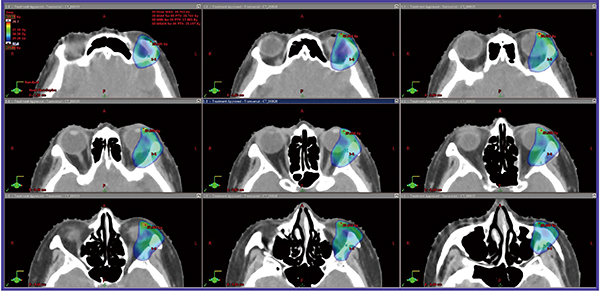

●症例2:眼窩原発の辺縁帯B細胞性リンパ腫MALT型 stageⅠ

重度の緑内障を合併していたのでCTVをできるだけ小さくした。RapidArcを用いて24 Gy/12回のISRTを行った。急性毒性として,軽微な結膜発赤を認めたのみであった。経過観察期間中に,白内障や涙量の減少はない。完全寛解を2年間維持している。線量分布図を図2に示す。

図2 症例2:眼窩原発の辺縁帯B細胞性リンパ腫MALT型 stageⅠに対するRapidArcを用いたISRTの例